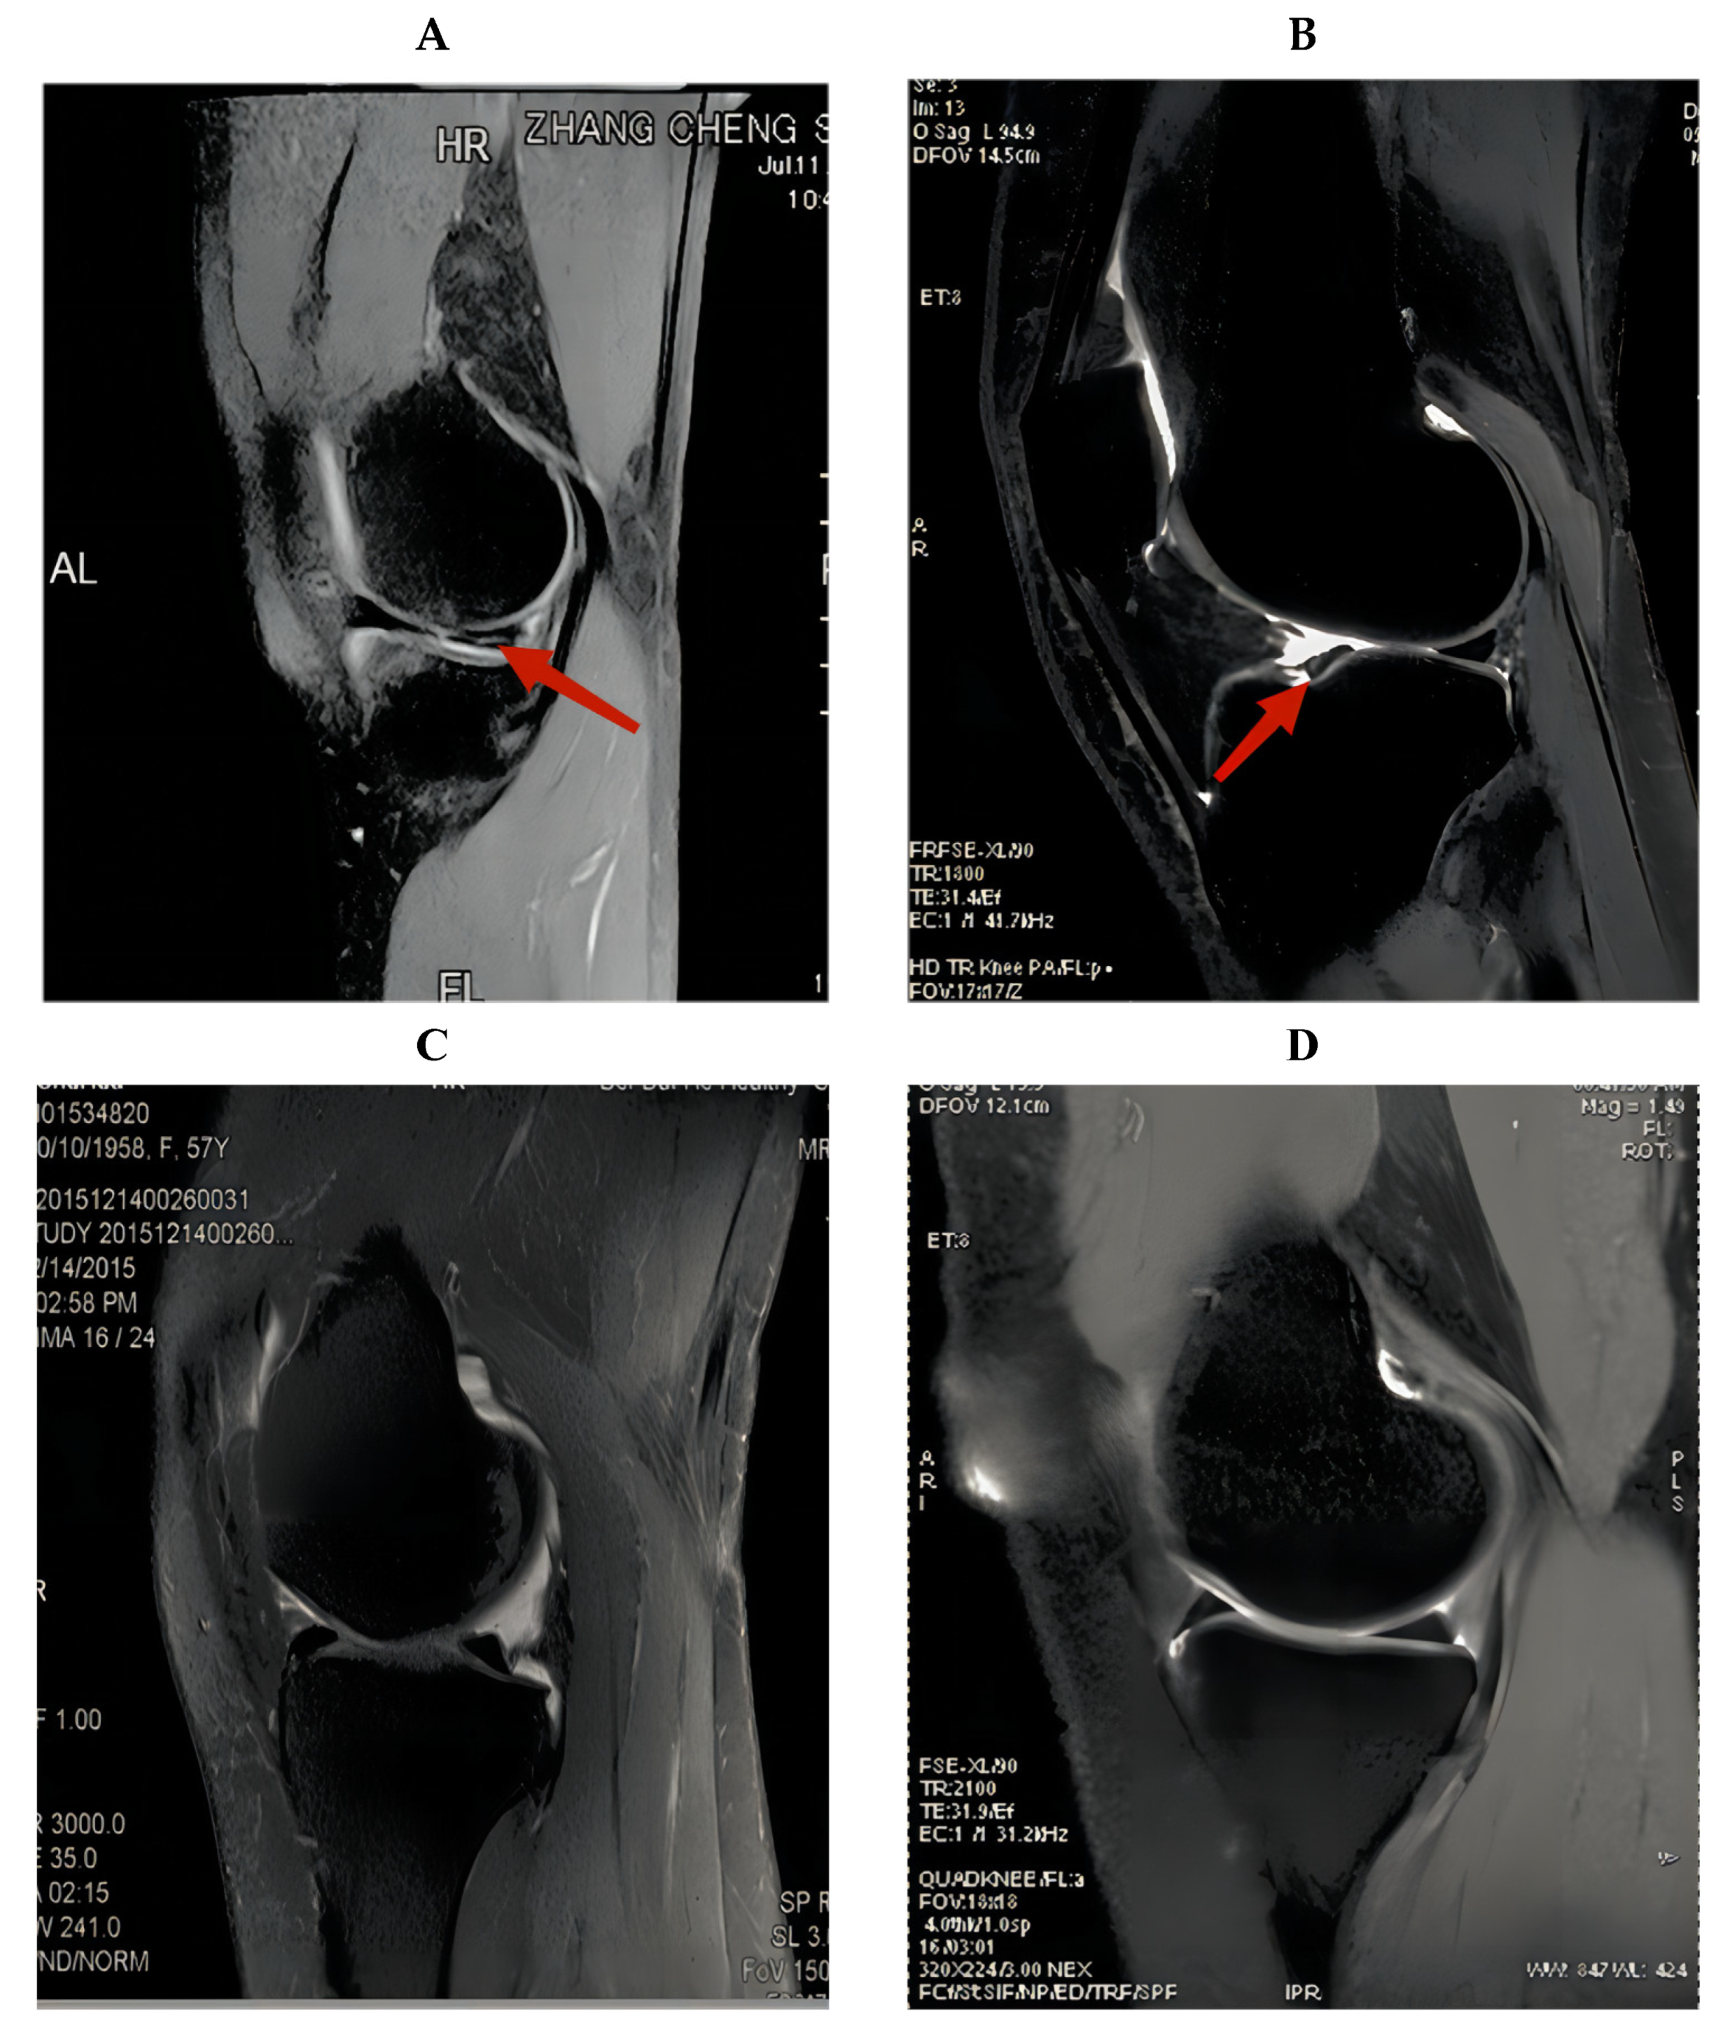

Figure 1. MRI images of knee joint with meniscus injury. (A) The posterior root injury of the meniscus. (B) The anterior root injury of the meniscus. (C,D) MRI images of knee joint without meniscus injury. The arrows point to the meniscus injury.

Patients who underwent surgery in our hospital and healthy patients who underwent MRI screening at our hospital were included. As there was no standard format for all MRI patient data, we selected the knee MRIs of 2000 patients from 2015 to 2021, excluding pixels that were too blurry to detect and patients with knee ligament injuries or other disorders. A total of 1396 knee MRI pictures were acquired, 716 of which were normal (Figure 2). For the remaining 680 pieces depicting meniscus injury, the age range was between 17 and 62 years (17–62 years). For all patients with meniscus injury in our hospital, the chief physician performed arthroscopic surgery, and the intraoperative diagnosis was the same as the MRI diagnosis of the radiologists. If a problem of knee joint meniscus and clean-up resection occurred, meniscus stitches were used. Figure 3 shows the intraoperative arthroscopic images of meniscus injury (Figure 3).